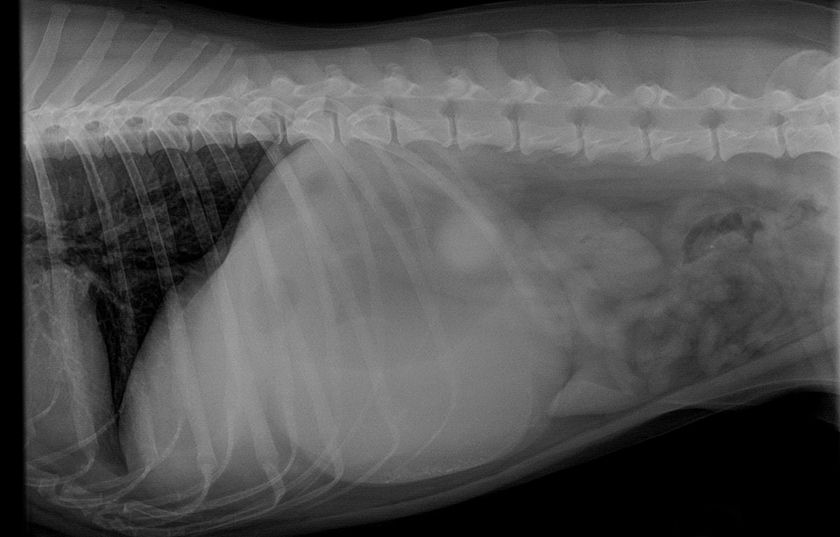

- Radiographie pulmonaire. Cet examen nous permet d'évaluer l'état des poumons et de détecter des signes d'inflammation, d'infiltration ou de liquide.

La dernière étape consiste à surveiller et à évaluer l'efficacité du traitement. Pour suivre l'évolution de l'état de santé de votre animal, des radiographies régulières peuvent être prescrites. Le traitement peut être effectué à domicile sous la supervision d'un vétérinaire. Il est important d'offrir à l'animal malade des conditions de vie adaptées, notamment une bonne hygiène, de la chaleur, du repos et une alimentation équilibrée de haute qualité.